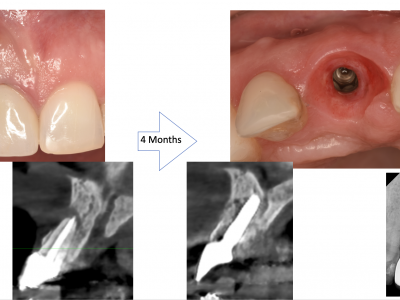

Each case is documented with clinical pictures before, after and during operation. For most of the cases there is surgical video. CBCT before, in the OP day and 4 months after, or longer period of time will demonstrate the volume of buccal bone and soft tissue. Depends of time available, between 13 and 20 clinical cases can be shown.